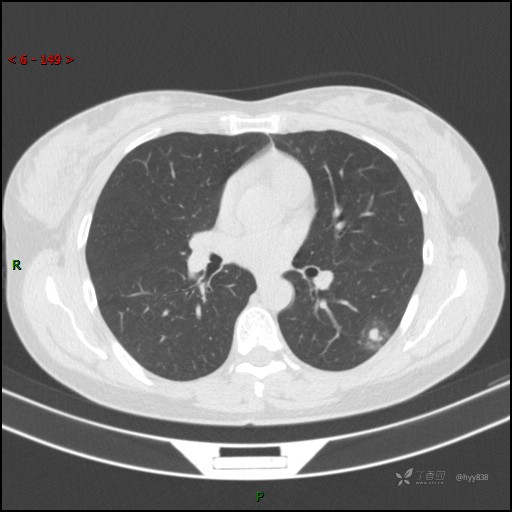

胸膜下“煎鸡蛋征”,感染 VS 炎症 VS 肿瘤,挑战有你---结果公布~

患者性别:女

患者年龄:46岁

简要病史:干咳半月伴左胸部不适

辅助检查:CT

临床诊断:结节

讨论:病变性质?